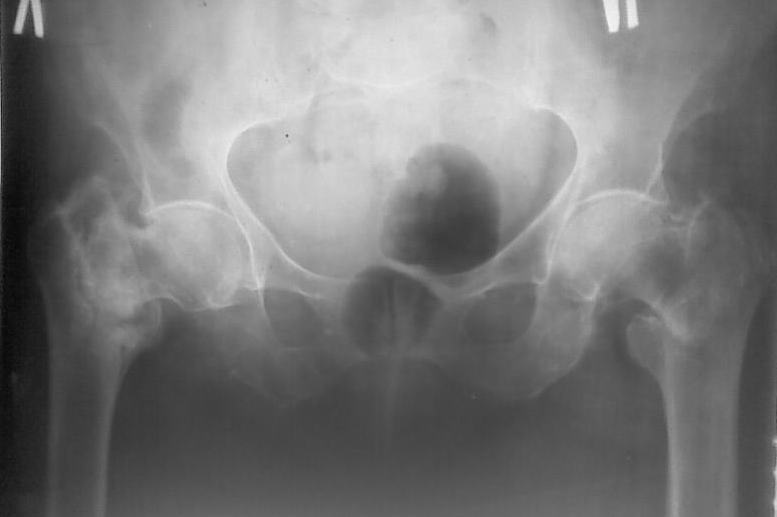

Поступила больная 80 лет, справа перелом свежий, слева - 4 летней давности.

Здравствуйте,уважаемые коллеги! Поступила больная 80 лет, справа перелом свежий, слева - нелеченный перелом 4х-летней давности. Больная проживает в частном доме, до последней травмы передвигалась с костылями, себя обслуживала.Соматически сохранна.

Помогите выбрать оптимальную тактику лечения (Гамма недоступна)

Наши варианты :

1. Справа DHS, слева - МВО, промежуток между операциями - 10 -12 суток

2. Справа DHS , слева - не трогать 3. Справа DHS . слева протез Мура после скелетного вытяжения (?)

Я больше склоняюсь к третьему варианту,поскольку установка протеза позволит максимально быстро поднять больную.